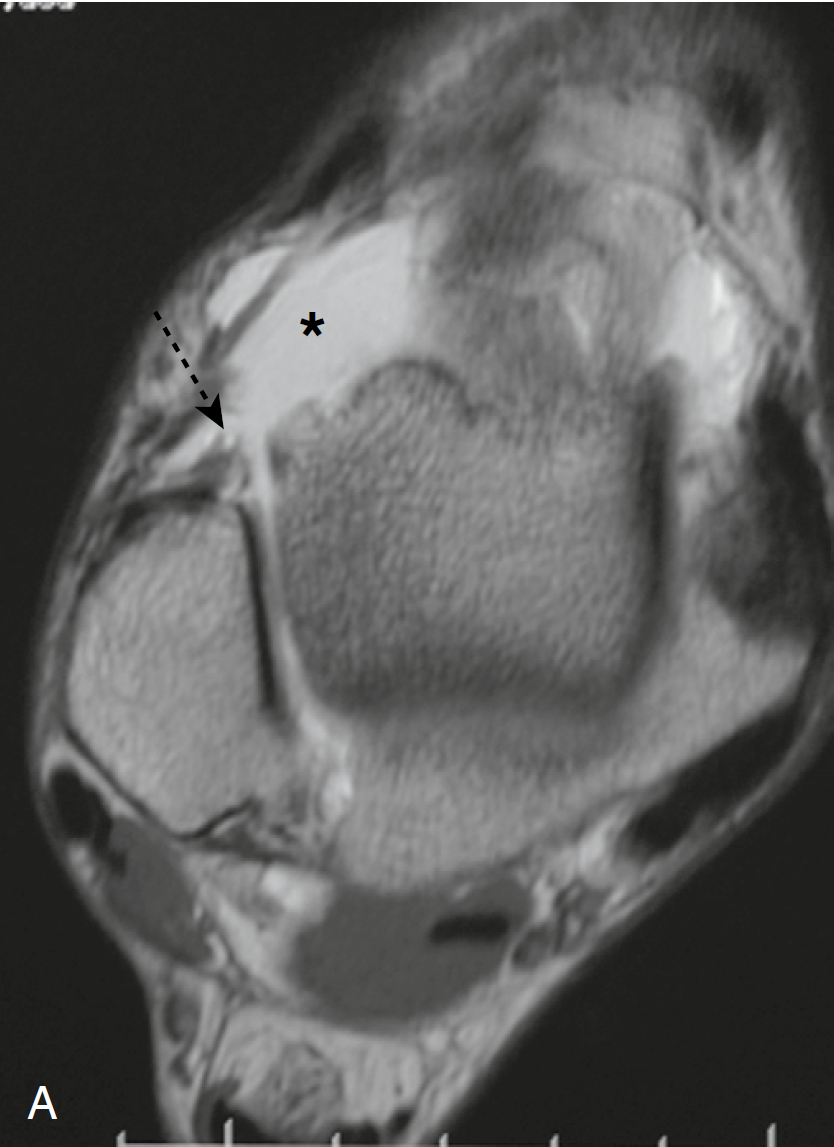

图2(A与B)连续轴位T1加权MR关节造影图像显示:距腓韧带完整断裂,只有一小近端残留物(虚箭头)。比正常关节部呈高信号(星号)